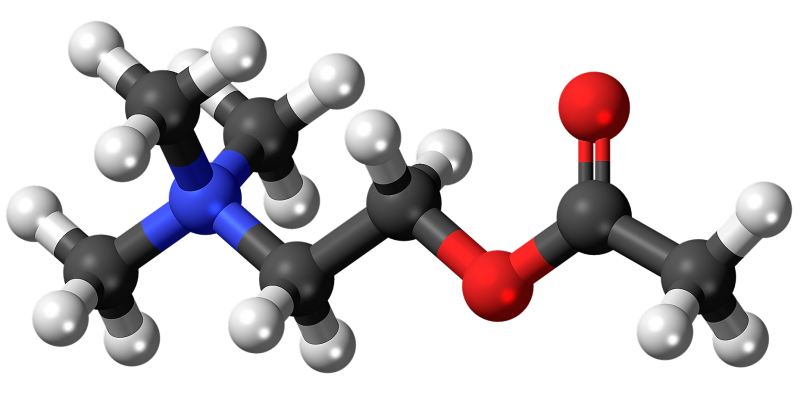

Cada caso de hiperaldosteronismo es distinto. Si no hay complicaciones, el individuo puede mejorar con medicinas como espironolactona (diurético) y eplerenona (para controlar la secreción de la aldosterona), entre otras. Todo dependerá del diagnóstico y del criterio clínico del especialista.